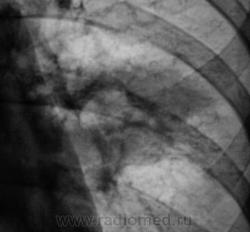

"Золушка" - сестра хозяйки ветки, тоже дочь "почившего".

Плеврит, естественно...тоже туберкулезный....